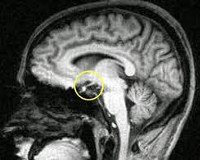

• Методы медицинской визуализации. Прицельный рентгенологический снимок турецкого седла позволяет выявить уменьшение размеров железы. Более подробную информацию о структуре и изменениях органа предоставляют томографические методики (МРТ, компьютерная томография).